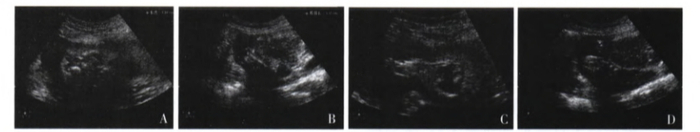

异常彩超结果:胎儿双上臂及肱骨、双前臂及尺、桡骨未见显像,双手显示不清。双侧大腿及其内的股骨可见,右侧股骨长约10.7mm(图2-A),左侧股骨长约33mm(图2-B),双侧小腿及其内的胫、腓骨缺如,胎儿双足可见,分别与其大腿直接相连(图2-C,图2-D)。羊水指数86mm。